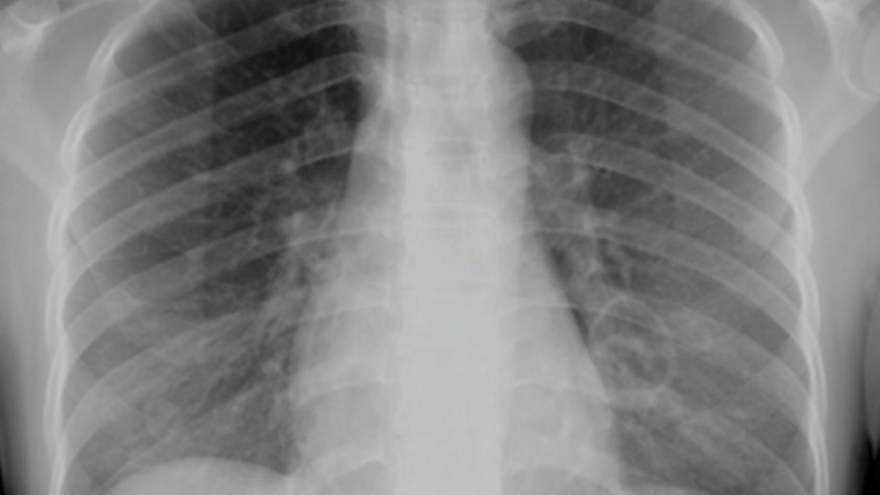

VOV.VN - Suốt 6 tháng sốt cao 39–40°C, sụt gần 20 kg và chữa trị ở nhiều bệnh viện trong nước lẫn Mỹ nhưng không tìm ra nguyên nhân, ông N. tưởng chừng không qua khỏi. Tại Bệnh viện Bệnh Nhiệt đới Trung ương, bác sĩ phát hiện cùng lúc 3 tác nhân nguy hiểm đang tấn công cơ thể ông.